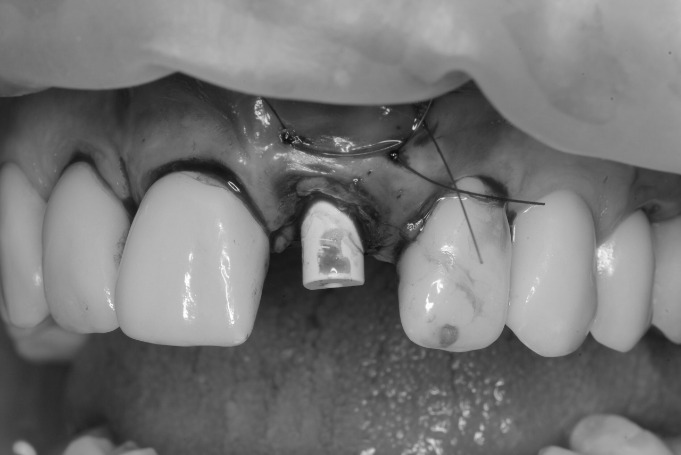

Hoy compartimos un impresionante caso clínico de cirugía guiada, ilustrado con fotos que documentan cada etapa del proceso. En el mismo día, removimos el diente dañado, realizamos injertos de tejido blando y hueso, colocamos el implante y un diente provisional. Como puedes ver en la última foto, el diente provisional se mimetiza perfectamente con los dientes naturales del paciente.

Este procedimiento se llevó a cabo de manera muy controlada y pausada, gracias a la cirugía guiada. Utilizamos una guía quirúrgica protésicamente planificada, que nos permite operar con una precisión excepcional, minimizando cualquier margen de error. Esta técnica es mucho más minuciosa y precisa en comparación con los métodos tradicionales.